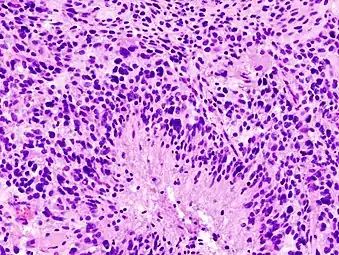

Histopathology of glioblastoma, showing high grade astrocytoma features of marked nuclear pleomorphism, multiple mitoses (one at white arrow) and multinucleated cells (one at black arrow), with cells having a patternless arrangement in a pink fibrillary background on H&E stain.

Lower magnification histopathology, showing necrosis surrounded by pseudopalisades of tumor cells, conferring a diagnosis of glioblastoma rather than anaplastic astrocytoma